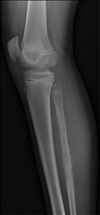

2

3